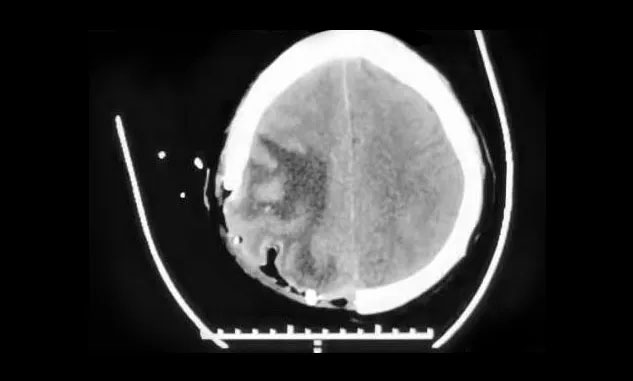

▲ 术后,中线结构恢复正常

术后,患者没有出现肢体运动障碍,头晕、头痛及呕吐消失,目前正在康复中。下一步,明确病理结果后,将继续MDT团队讨论,确定治疗方案。